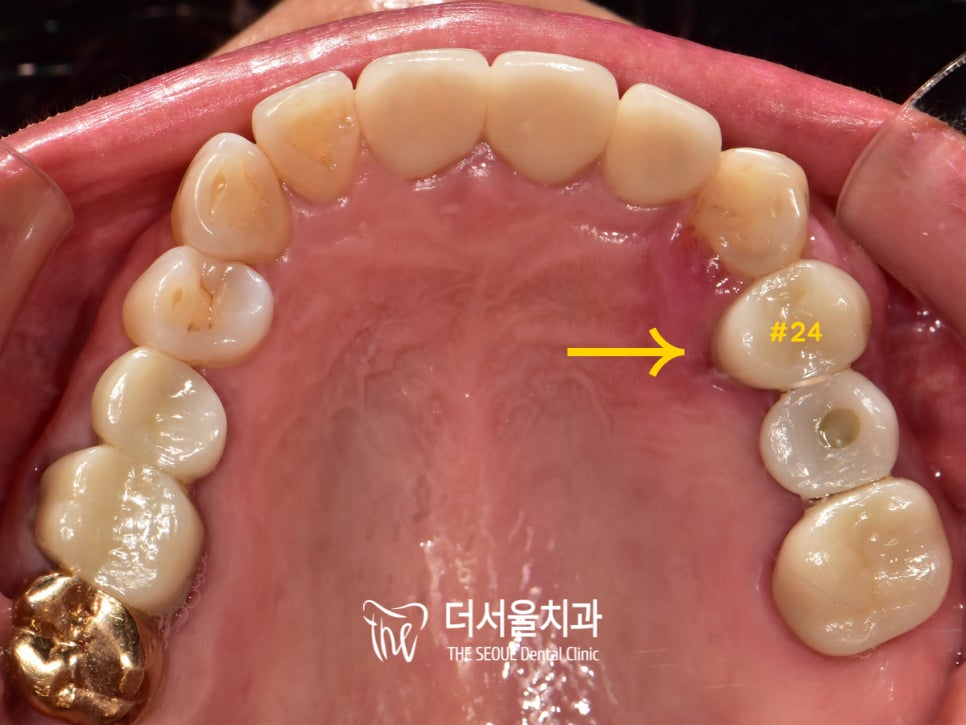

자, 실제 환자의 구강 내부를 살펴보았습니다.

# 25는 전에 열심~히 심어드렸던 디지털 임플란트 네요ㅎㅎ

어 그런데?

그 옆인 # 24가 문제가 있어 보입니다.

잇몸을 봐도 퉁퉁 부어있으며

색까지 보랏빛으로 변해있었는데요.

육안으로 확인했을 땐